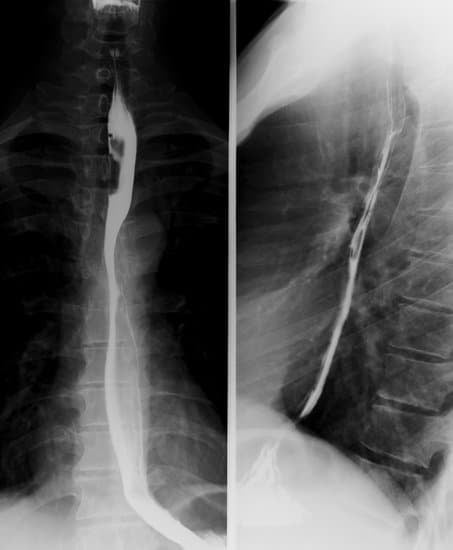

바륨 식도조영술 (Barium Swallow)에 대한 이해

바륨 식도조영술(Barium Swallow)은 바륨(Barium)이라는 방사선 불투과성 물질을 삼킨 후 X-ray를 촬영하여 식도, 위, 십이지장의 구조와 기능을 평가하는 영상 검사입니다.

바륨 혼합액 섭취: 환자는 방사선 불투과성 물질인 바륨 혼합액을 삼킵니다.

X-ray 촬영: 바륨이 식도를 통과하는 동안 연속적으로 X-ray를 촬영하여 식도의 모양과 움직임을 관찰합니다.

위치 조정: 환자는 다양한 자세(서기, 눕기 등)를 취하여 여러 각도에서 식도를 촬영합니다.

이미지 분석: 촬영된 X-ray 이미지를 통해 식도의 구조와 기능을 평가합니다.